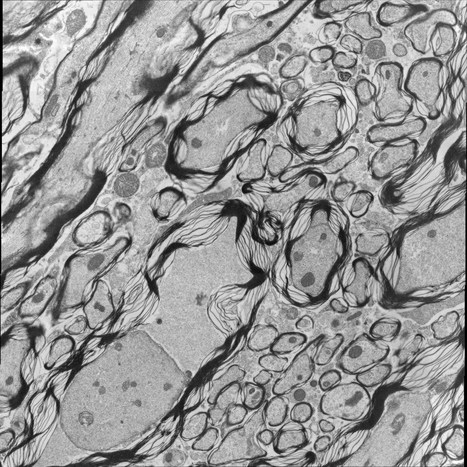

For image analogies based image registration, I have corresponding TEM/Confocal Microscopic image pairs of mouse brains with corresponding regions highlighted by a box. Using the correlative microscopy technique on the mouse brain, I want to localize specific brain regions associated with Pelizaeus-Merzbacher Disease (PMD) and do quantitative assessment of hypomyelination and demyelination in mice. PMD is one of a group of genetic disorders characterized by progressive degeneration of the white matter of the brain affecting the myelin sheath, the fatty covering that acts as an insulator on nerve fibers in the central nervous system.

The confocal microscopy images are multichannel color images in our test dataset. The blue channel is based on the blue stain DAPI (a fluorescent stain) which stains the DNA of the cell nucleus and corresponds to dark regions within the nuclei in the TEM. The green channel is based on the stains of the myelin sheats, visible as dark black layers covering the neurons in the TEM images. The red channel is not explicitly stained for and is caused by the auto-fluorescent effect of lipofuscin. The confocal image with RGB channels and its corresponding TEM image are shown in Fig. 5.

Currently I have six pairs of 2D TEM/confocal images with resolutions 582.24 pixels per μm𝜇𝑚\mu m and 7.5887.5887.588 pixels per μm𝜇𝑚\mu m respectively (1μm=1micron=106m1𝜇𝑚1𝑚𝑖𝑐𝑟𝑜𝑛superscript106𝑚1\,\mu m=1\,micron=10^{-6}\,m). The resolution is different between two images and only a small region in the confocal image corresponds to the TEM image.

5.3 Image Analogies based Image Registration

5.3.1 Pre-processing

In the pre-processing step, I extract the corresponding region of the confocal image and resample both confocal and TEM images to an intermediate resolution. The final resolution is 14.52 pixels per μm𝜇𝑚\mu m, and the image size is about 200×200200200200\times 200 pixels, which is dependent on the original TEM image size.

From the example in Fig. 5, the blue and red channels are too noisy and contain less information compared to the green channel. We use only the green channel as grayscale image for the registration in our application. The datasets are roughly registered based on manually labeled landmarks with a similarity transformation model.

Refer to caption

(a) Red channel of confocal image

(b) Green channel of confocal image

(c) Blue channel of confocal image

(d) Grayscale of confocal image

(e) Confocal image

(f) TEM image

Figure 5: Example of Confocal image with RGB channels and TEM image